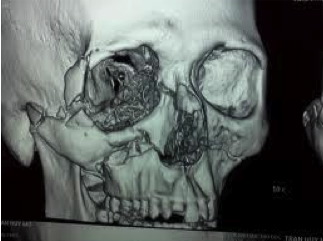

Hospital-Based Computed Tomography (CT)

Computed tomography (CT) uses a narrowly collimated beam of x-rays that rotates in a full arc around the patient to produce an image of detailed cross-secional slices. A major advantage of CT is its ability to image bone, soft tissue and blood vessels all at the same time. An array of detectors, positioned at several angles, records those x-rays that pass through the body. The image is created by a computer that calculates tissue absorption and can produce three dimensional reconstructed images representing tissues that demonstrates the densities of the various structures. CT is less sensitive to patient movement than MRI. CT can be performed if you have an implant medical device of any kind, unlike MRI.

Tumor masses, infarctions, bone displacement, and accumulations of fluid may be detected. It is useful for the diagnosis of bony abnormalities including fractures, dislocations, arthritides, ankylosis, and neoplasia. Three dimensional reconstructed images can be produced.